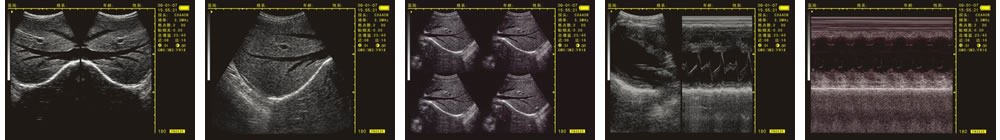

優(yōu)質(zhì)的成像效果